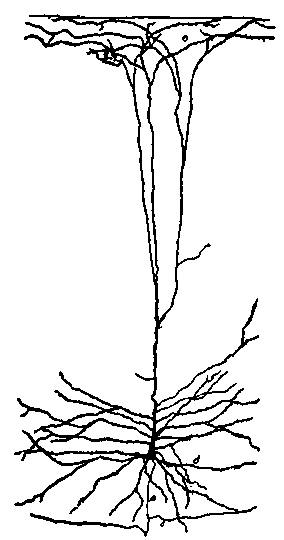

| 2. | Cortex of human brain illustrating complexity of the systems and plexuses of nerve fibers | 109 |

| 3. | Small and medium-sized pyramidal cells of the visual cortex of a child twenty days old | 110 |

| 4. | Series of sections showing the fine nerve endings and branchings of the first and second layer of the visual cortex of a child fifteen days old. | 111 |

| 5. | First, second and third layer of the anterior central convolution of the brain of a child one month old | 112 |

| 6. | Layers of the posterior central or ascending parietal convolution of a new-born child | 112 |

| 7. | Diagram of cells of cerebral cortex | 113 |

| 8. | Scheme of lower motor neuron | 114 |

| 11. | Isolated cell from human spinal cord | 117 |

| 12. | Neuron from the optic lobe of the embryo chick | 118 |

| 13. | Deep layer of giant pyramidal cells of the posterior central or ascending parietal convolution of a child thirty days old | 119 |

| 14. | Pyramidal cell of cerebral cortex of mouse | 119 |

| 20. | Complexity of cell of the central nervous system | 131 |

| 21. | Section through the cortex of the gyrus occipitalis superior | 132 |

| 22. | Motor cell of ventral horn of spinal cord from the human fetus | 133 |